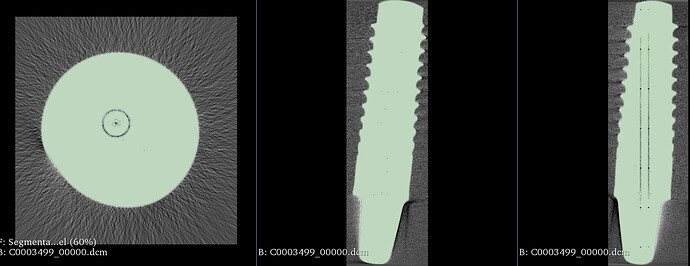

I uploaded an example of the manual transformation outcome…

I am trying to register a microCT scan of an implant with a conv. CT of the same implant within the jaw.

I transformed the microCT scan to the correct position however the final 3d-3d registration fails. Even when I resample the microCT image to the same voxel sizes (which means a significant reduction of the visualization of the implant).